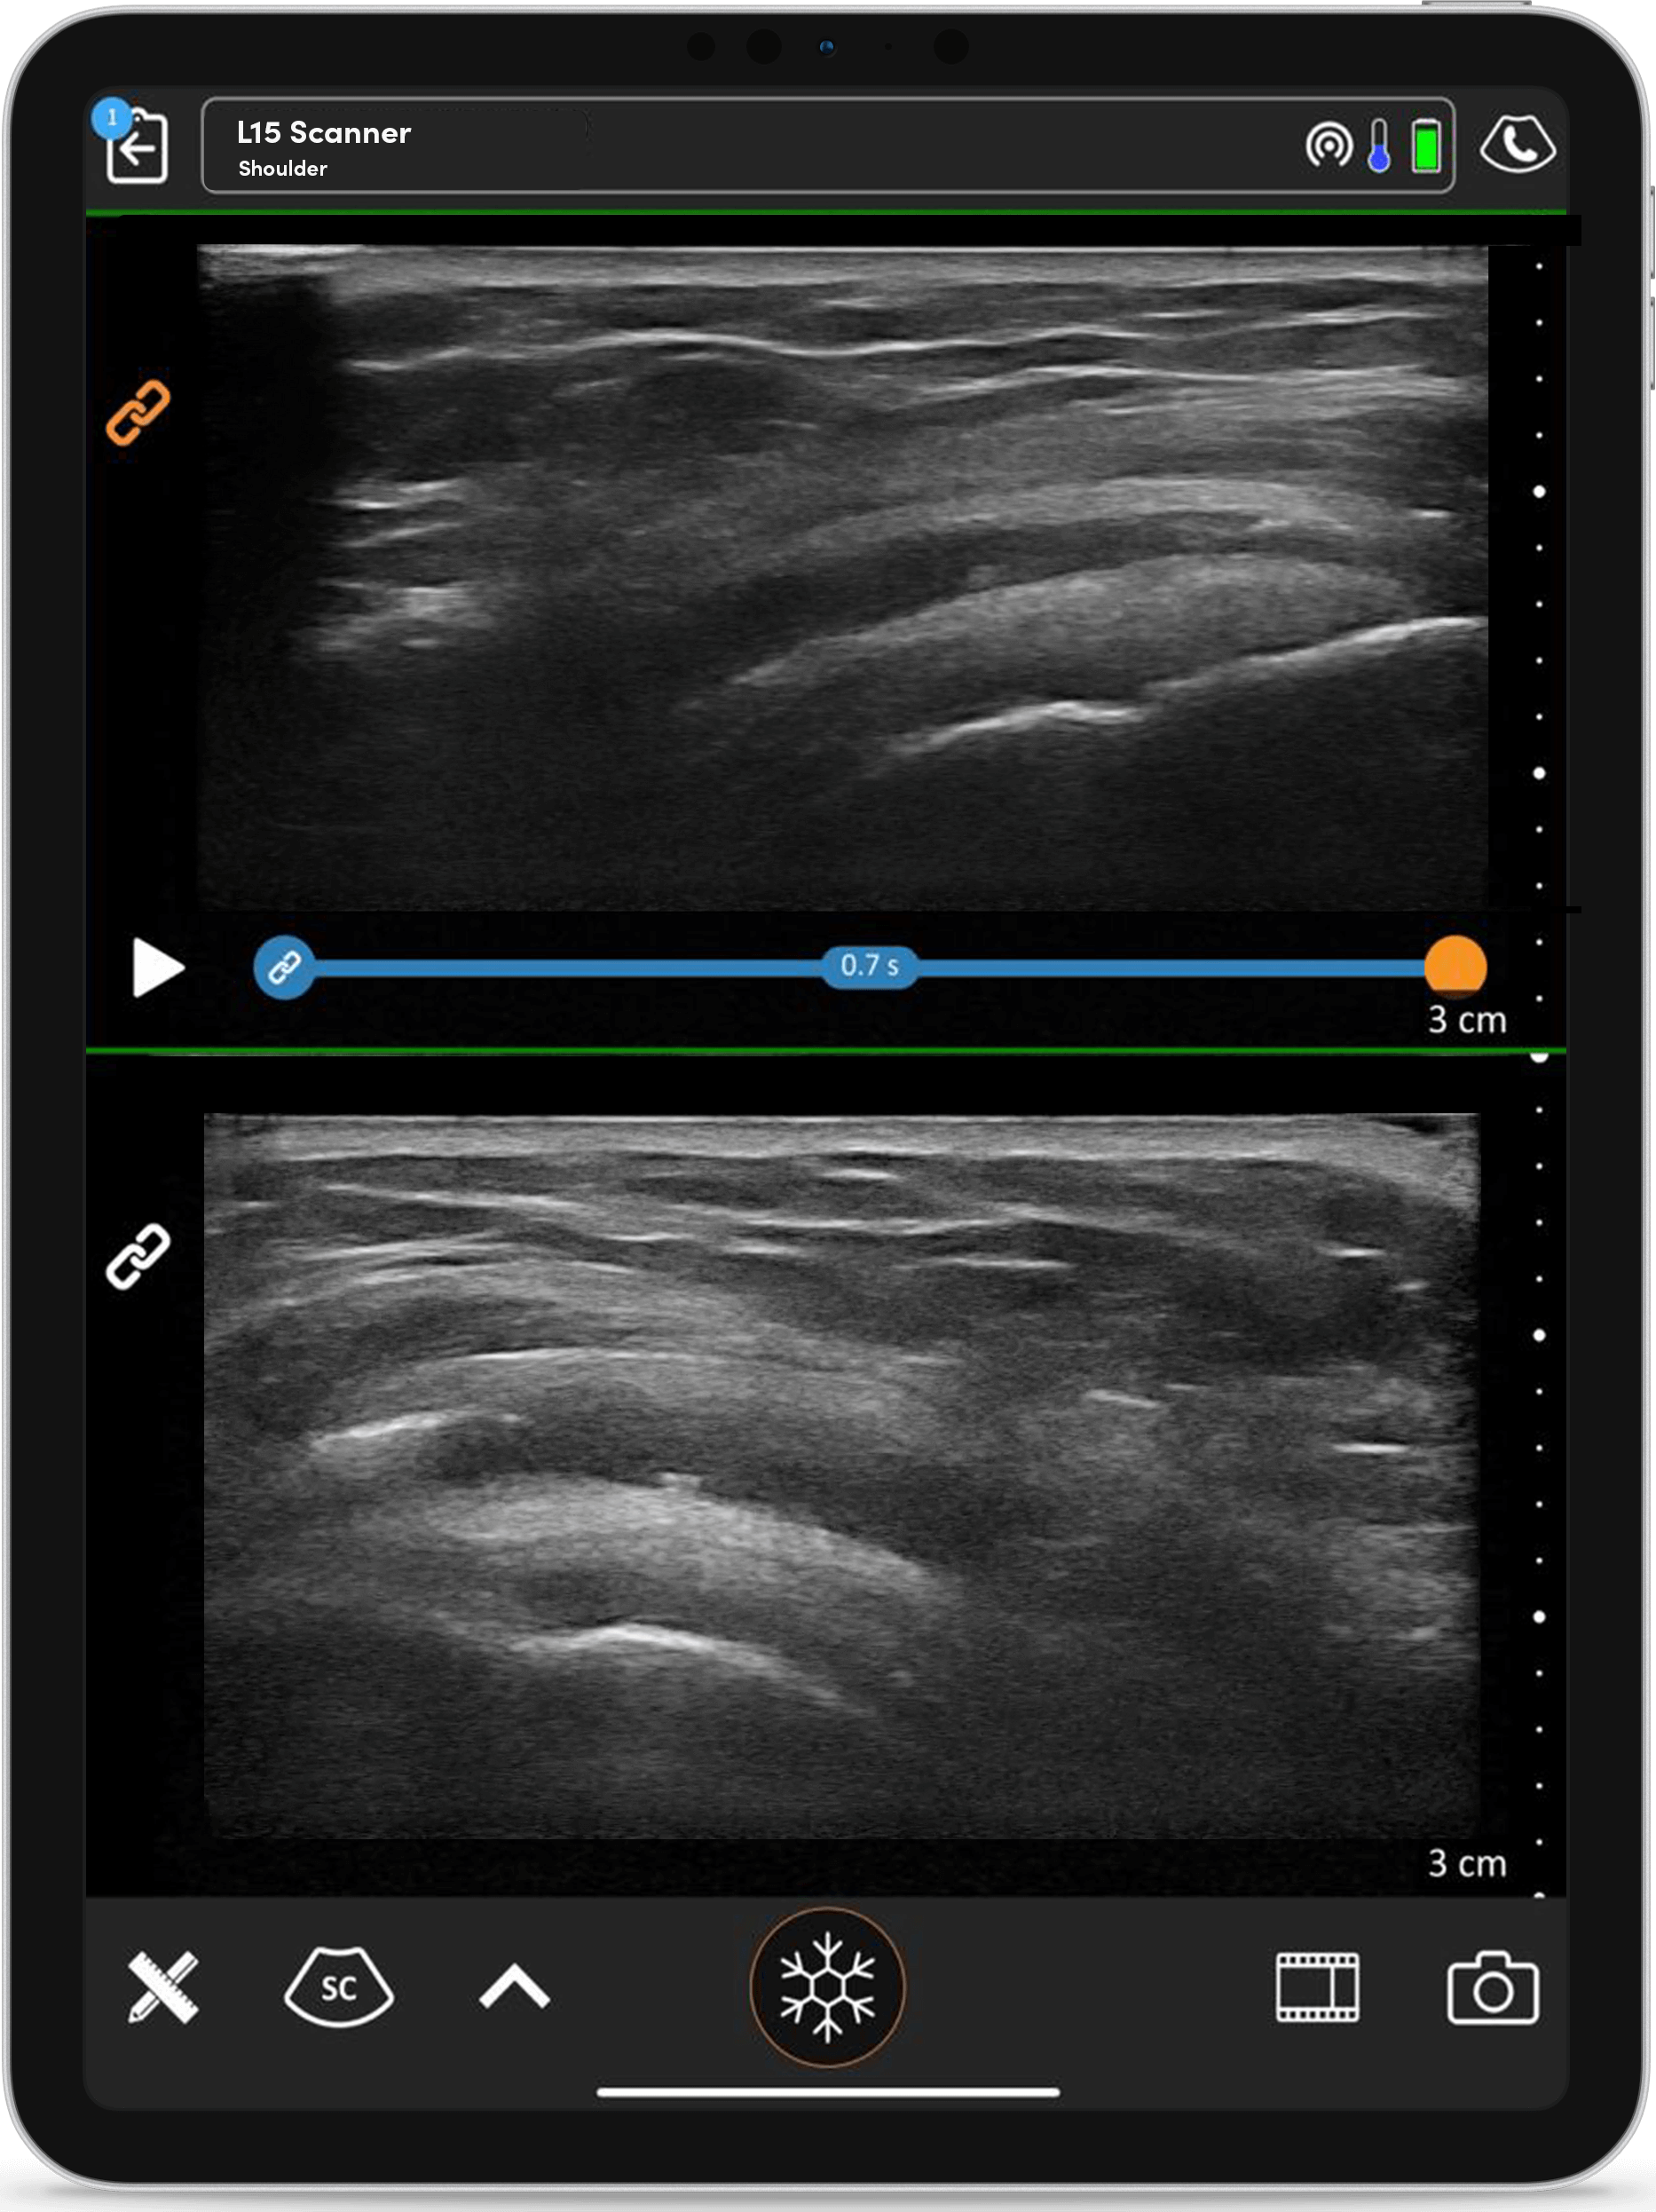

Profitez de la possibilité d’afficher à la fois l’axe long et l’axe court ou encore de comparer l’anatomie gauche avec l’anatomie droite.